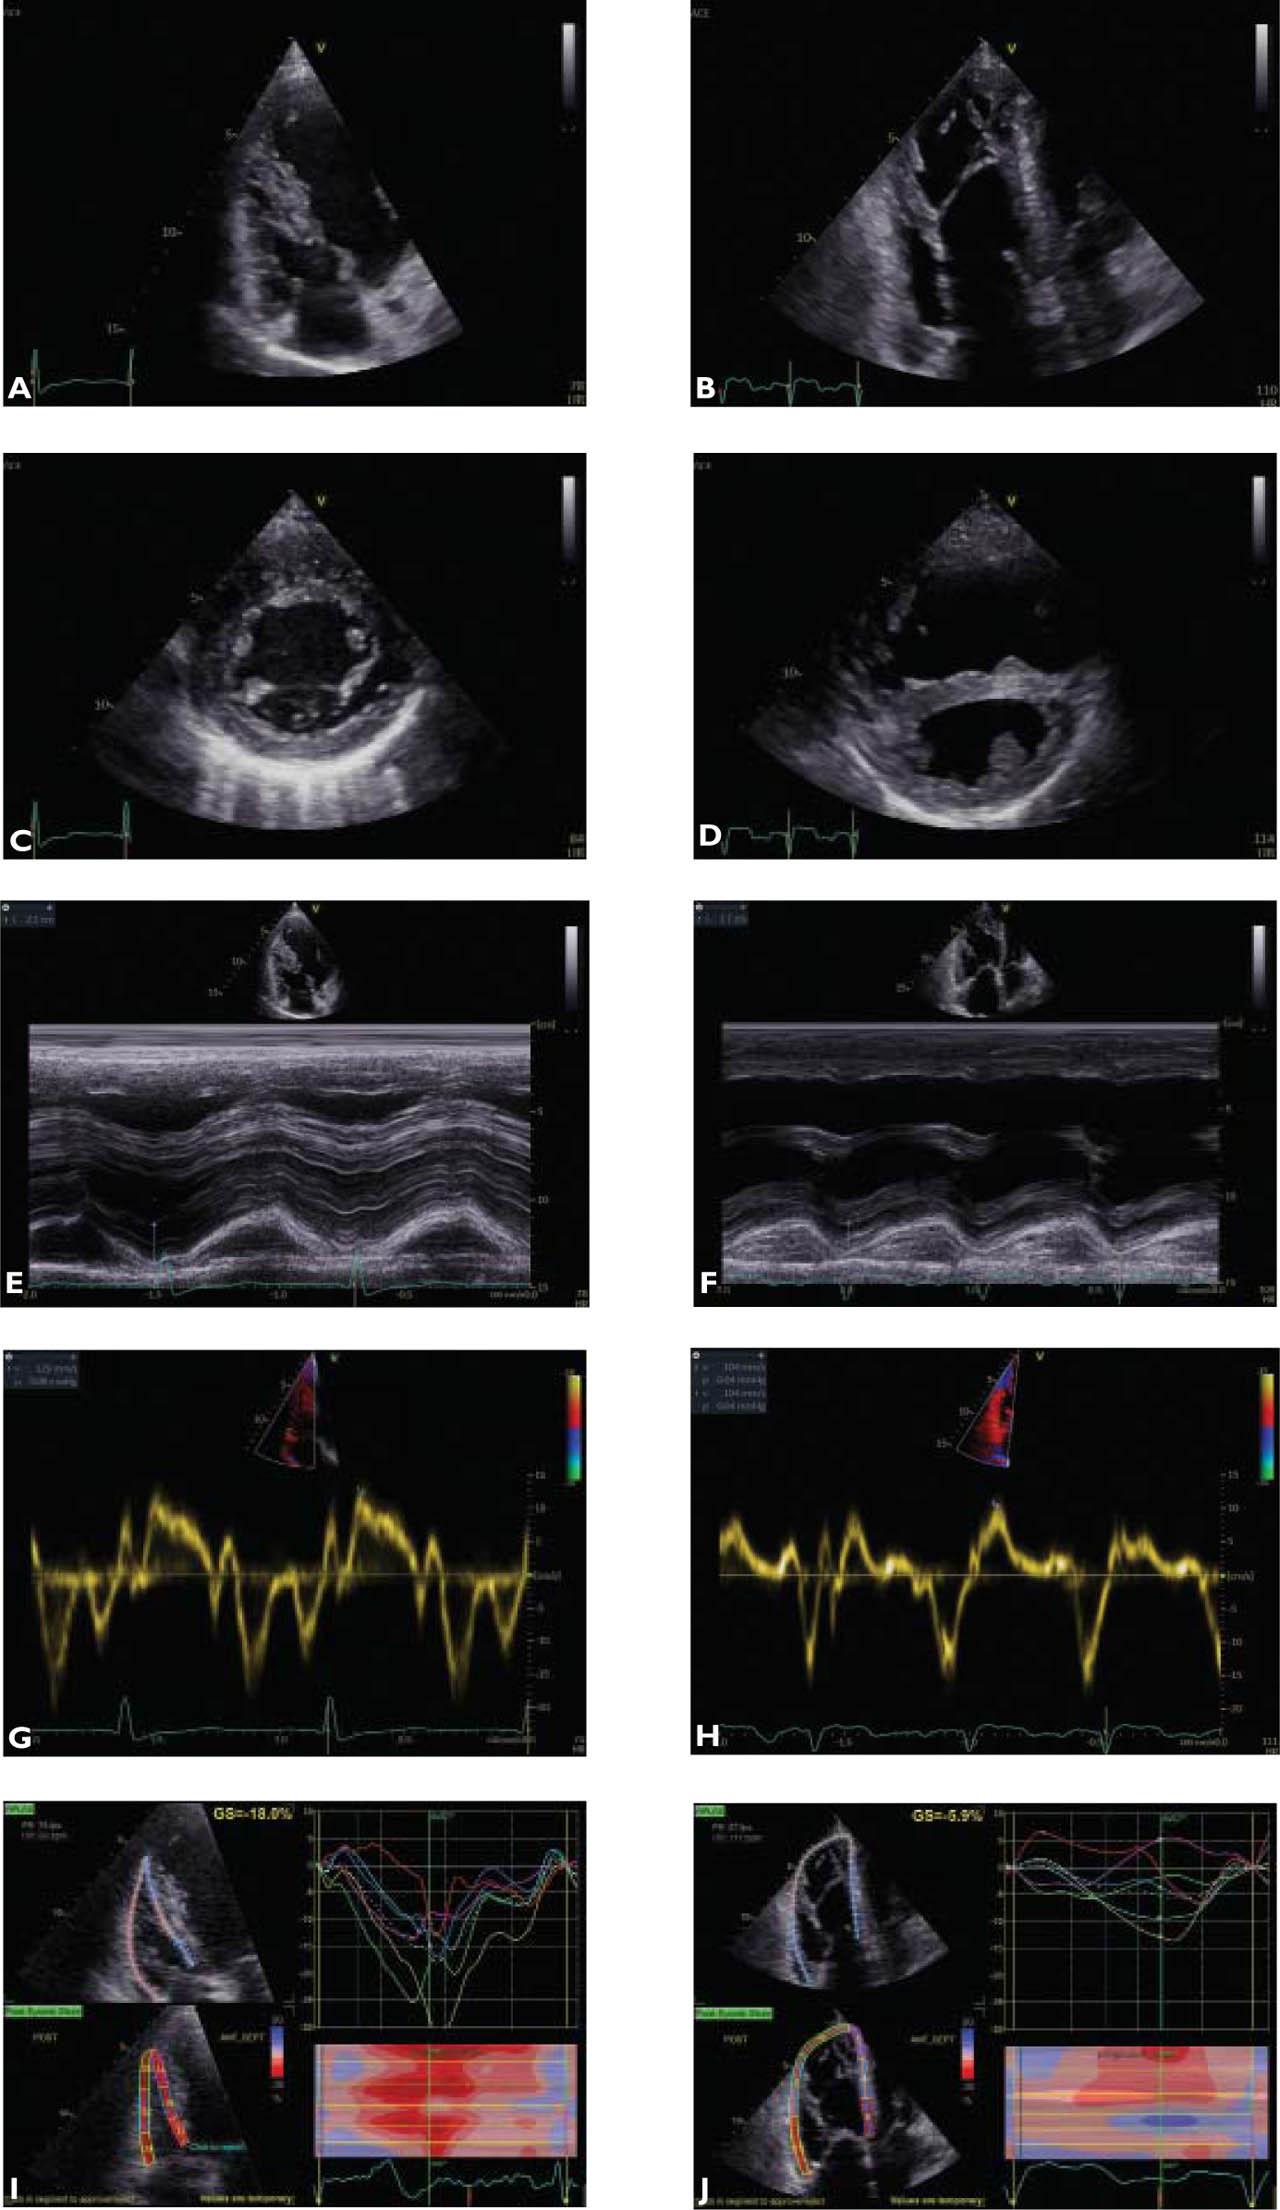

Figure 1